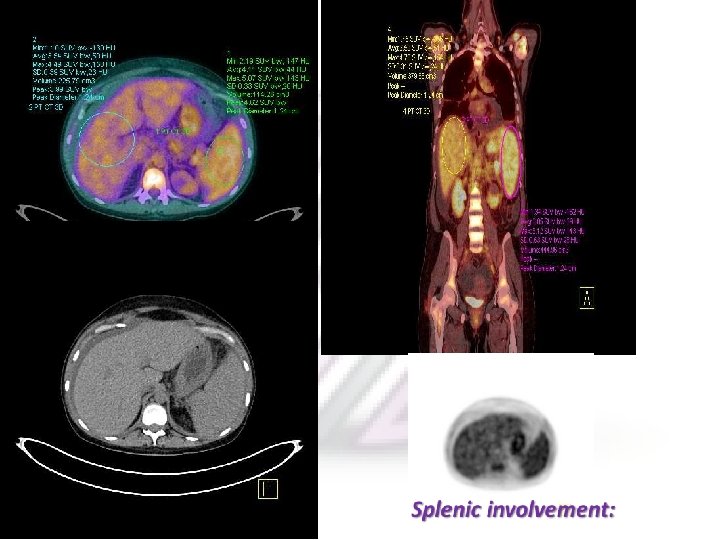

The LUGANO Classification PET may upstage or pick up occult lesions such as splenic, bone marrow , osseous, and gastrointestinal involvement which may otherwise be missed on conventional CT.

Maximal intensity projection (MIP) image in a patient of diffuse large B-cell lymphoma (DLBCL) shows extensive sites of involvement visualized as areas of increased FDG uptake. Transaxial CT images Show axillary and abdominal LAP and a large subcutaneous nodule. Fused PET/CT images show sites of Main advantage over anatomical imaging techniques, such as CT, is its ability to bone marrow involvement in the sternum, spine, and iliac crest, detect metabolic changes in the areas involved with malignant lymphoma before the structural changes become visible. over and above the lesions picked up on CT Usefulness of 18 F-FDG PET in the Initial Staging of Lymphoma